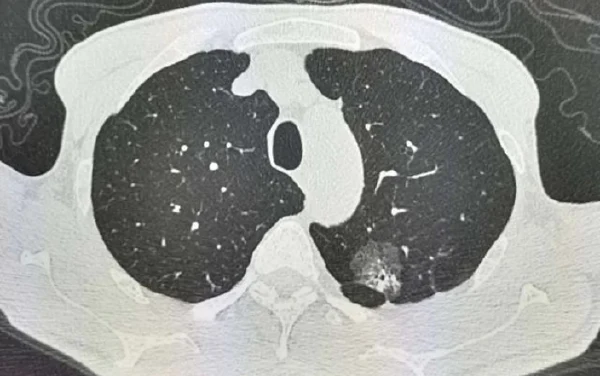

肺结节和肺腺癌的诊断通常需要综合临床表现、影像学检查、美学检验和病理结果。影像学检查包括胸部CT、PET-CT等,可以提供直观的肺部影像信息。

依据最新的临床研究,影像学特征如结节大小、形状、密度等,以及病理特征如浸润性、胸膜受累等,都是判断结节性质的重要依据。影像学检查要与其他检查结果综合分析,避免单一指标误导。